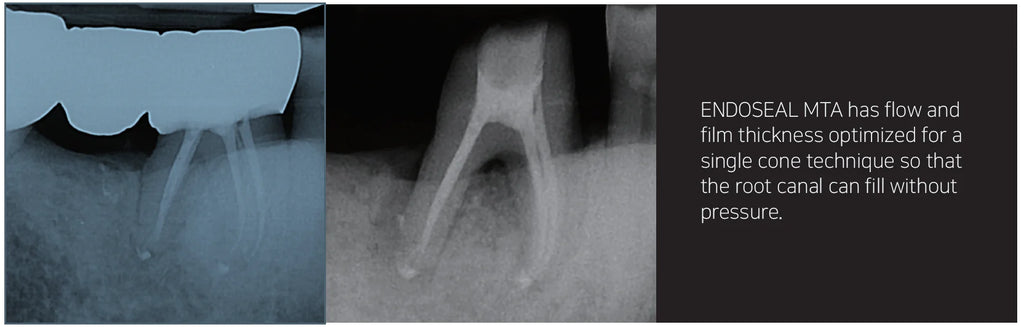

ENDOSEAL MTA is a paste-type root canal sealer based on pozzolan cement that has excellent physical and biological properties of MTA. It is premixed and pre-loaded in a syringe that allows direct application of the sealer into the root canal without requiring powder/liquid mixing, unlike other products. The product has outstanding flowability and maneuverability, which makes it possible to completely fill the root canal system including accessory and lateral canals. It is eugenol-free and will not impede adhesion inside the root canal.

ENDOSEAL MTA is developed for root canal filling and root perforation repair, effectively preventing periapical tissue irritation as well as secondary infection.